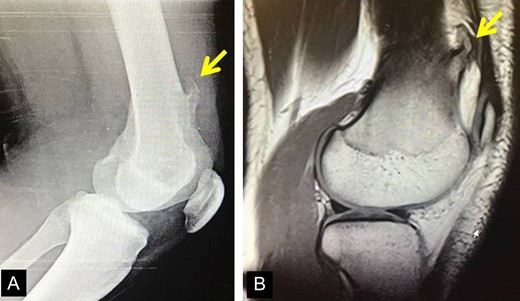

X-rays revealed an extra-articular mass at the medial aspect of the distal femur (Fig. 1A). Magnetic resonance imaging (MRI) confirmed the radiograph findings and no meniscal and ligament rupture or chondral defects were revealed. These characteristics were consistent with osteochondroma (Fig. 1B). Under general anesthesia, a standard antero-lateral portal used to access arthroscopically the knee. Cartilage surface, cruciate ligaments and menisci were normal. The osteochondroma was located extra-articularly, at the medial supracondylar side of the distal femur. Through a supero-medial portal and by perforating the capsule and a part of a medialis vastus muscle, the extra-articular lesion was reached arthroscopically (Fig. 2A). With an osteotome, the lesion was resected and removed with a grasper through the supero-medial portal (Fig. 2B). The remaining bony surface was abraded by a motorized shaver (Fig. 2C). The exostosis had maximum dimensions 3.1 × 2.5 cm. Histopathological examination confirmed the osteochondroma diagnosis.

(A) The X-ray depicting the exostosis (yellow arrow), (B) MRI depiction of the exostosis.